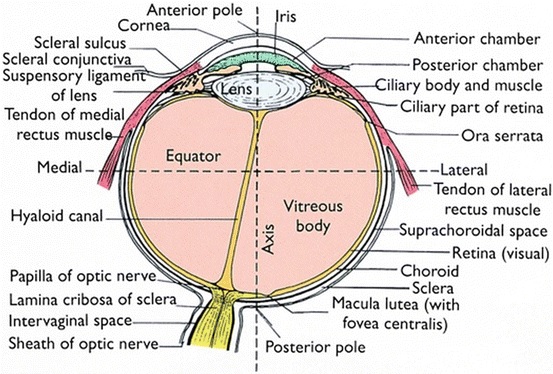

To understand what works and how, we need knowledge of the anatomy of the eye.

要了解什么有效以及如何起作用,我们需要了解眼睛的解剖结构。

The retina (retina) of the eye is the inner membrane, therefore, to inspect it, you need to look into the eye cavity through the pupil. The wider the pupil, the more the surface of the retina will be able to see the ophthalmologist. Therefore, to examine the fundus in the maximum amount, you need to bury the drops that can cause cycloplegia — a condition where the pupil is wide and does not respond to light. This reversible state, albeit a rather unpleasant one, passes in a couple of hours, but it makes it possible to look into the most “secret” zones of the retina.

眼睛的视网膜是内膜,因此,要检查它,您需要通过瞳Kong观察眼腔。 瞳Kong越宽,视网膜表面越能见到眼科医生。 因此,要检查最大量的眼底,您需要掩盖可能导致睫状肌麻痹的滴剂,这种情况是瞳Kong宽而对光没有React的情况。 这种可逆的状态虽然令人不快,但在几个小时内就过去了,但它可以观察到视网膜最“秘密”的区域。

The human retina consists of two parts.

人体视网膜由两部分组成。

The back is photosensitive; front end — not sensitive to light. Conventionally, the separation takes place «at the equator»: the department after the equator is the visual, or functionally active part of the retina, the neuronal retina, which we see. We don’t see a department around the equator, and problems arise there.

背面是光敏的; 前端-对光不敏感。 按照惯例,分离发生在“赤道”:赤道之后的部分是我们看到的视网膜的视觉或功能活跃部分,即神经元视网膜。 我们在赤道周围没有部门,那里出现了问题。

The visual part of the retina is its posterior, or photosensitive, section, a complex structure containing at least 15 types of neurons connected to each other by intercellular connections with well-developed microvilli and closure belts. These specialized compounds provide the difference in electrical potential due to the transport of ions between the surfaces. Through the intermediate layer, including conductor neurons, these cells send processes to the brain. These processes converge in the papilla of the optic nerve, forming the optic nerve.

视网膜的视觉部分是其后部或感光部分,是一个复杂的结构,包含至少15种神经元,这些神经元通过与发达的微绒毛和闭合带的细胞间连接相互连接。 这些专门的化合物由于离子在表面之间的传输而提供了电位差。 这些细胞通过包括导体神经元在内的中间层将过程发送至大脑。 这些过程会聚在视神经乳头中,形成视神经。

But since none of these types of outgrowths are anatomically connected with photoreceptors, these areas can easily be separated from each other, for example, when retinal detachment develops.

但是,由于这些类型的产物均未在解剖学上与感光体相连,因此,例如在视网膜脱离发展时,这些区域很容易彼此分离。